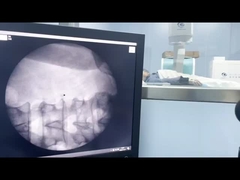

Sistema de localización por ultrasonido de máquinas ESWL de alto rendimiento certificado CE / ISO / CFDA

El sistema de detección de ultrasonido de alta eficiencia de China se ha certificado en el sitio web de la FDA.